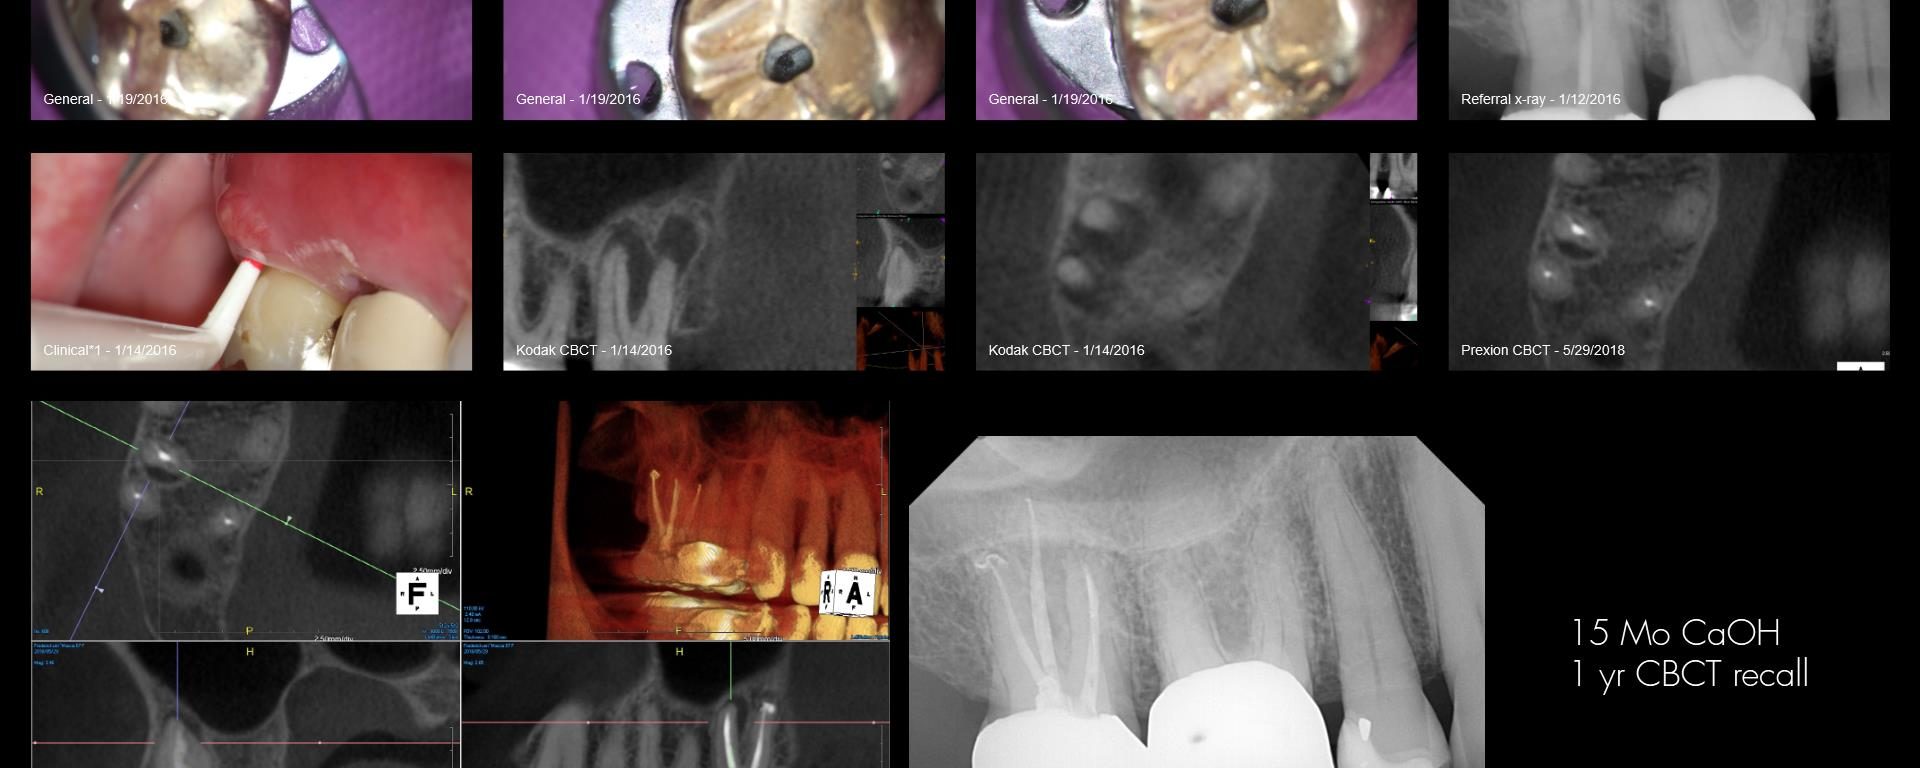

Because this was a Zirconia crown, my approach was to make a “staging platform” where I thought the access points would be. Proabbaly made the platform larger than I needed to. In this case, the X-nav was spot-on. I’m nowhere near Charles or Pushpak, but I am getting more comfortable with it. This took longer […]